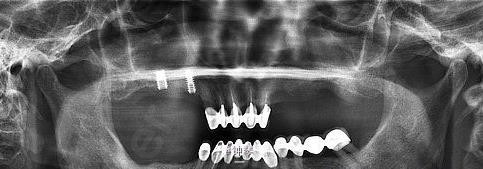

患者,女,左上颌3、4、6要求种植。平素体质一般,否认高血压、糖尿病及心脏病史,否认肝炎、结核病史,无药物、食物过敏史,无外伤、手术及输血史。

左上3、4、6种植